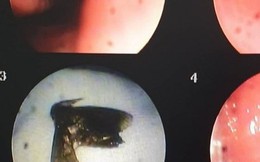

Ăn bọ xít, gia đình 7 người nhập viện cấp cứu

Phòng & chữa bệnh 18:00 12/08/2021

Sau khi ăn bọ xít đã chế biến, cả gia đình anh K. gồm 7 người có biểu hiện ngộ độc thực phẩm. Anh K. bị nặng nhất nên chuyển đến BV Bạch Mai (Hà Nội), còn những người khác được điều trị ở y tế cơ sở.